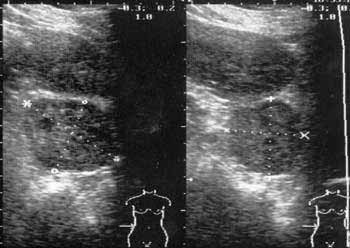

Рис. 4. Опухоль надпочечника с неоднородной структурой.